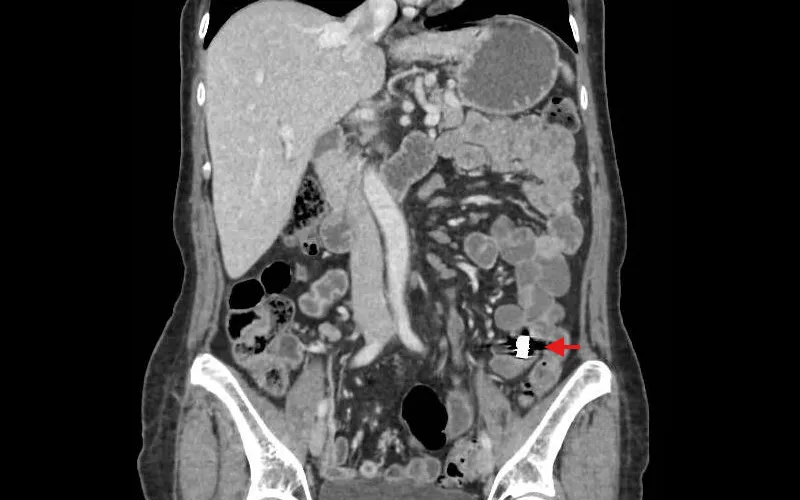

CT imaging showing lodged capsule

CT imaging showing the capsule lodged in the patient’s intestine.